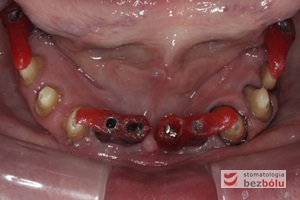

Żuchwa - widok powierzchni okluzyjnej - symetryczne braki zębowe w zakresie 4 siekaczy i trzonowców

Żuchwa – widok powierzchni okluzyjnej – symetryczne braki zębowe w zakresie 4 siekaczy i trzonowców

Braki zębowe w strefach bocznych szczęki i żuchwy - widoczne starcie patologiczne na skutek przeciążeń okluzyjnych w odcinku przednim

Braki zębowe w strefach bocznych szczęki i żuchwy – widoczne starcie patologiczne na skutek przeciążeń okluzyjnych w odcinku przednim